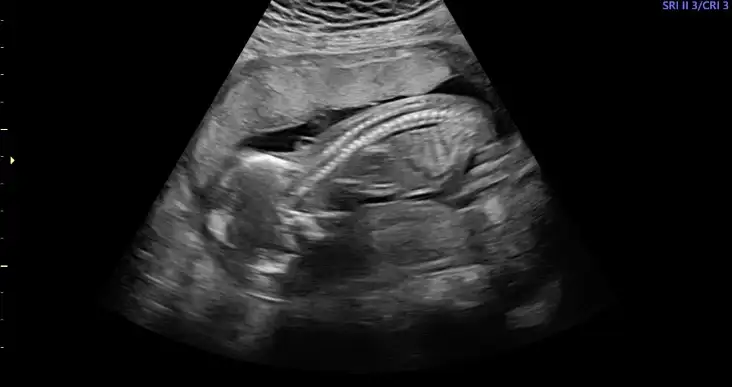

Cnm ayna gibi usg hep yüsütüydü asla kıpırdamadı neden dedim uyuyor dedi banada hiç bilgi vermez vermedi direk kız dedi kesin mi dedim kesin dedi, sinir oldum insan bir uyandırır zorlar falan 10dk bakmadı ama fotoda kız gibi yinede 20yi bekliyorum düzgün göreyim anlatsın bi doktorda ya bak fotolarıma, şu son fotoda bacak arası gözüküyor ama emin olamıyorum çünkü göstermedi doktor şurası şu diyeYüz üstü olduğunu nerden anlıyorsun canım. Ben hiçbirşey anlamıyorum ya. Doktor da demiyor şu pozisyonda becak arası şu organ var eli şu kolu şu. Son gittiğimdeki doktor söyledi sadece o da 2 dakika baktı bakmadı kalktım.

Hngisiymiş pipiKizlar beni bile tereddutte biraktirdiniz cinsiyet konusunda aksam aksam ultrasyon resmine baktimdegisirmi bilemiyorum artik ayrintiliya daha var doktor pipisi bu dedi sag tarafa bakin

Kiz kafasi obur taraftabu alt bolumu bacak arasiymis orasi degisirmi dedim bak simdi burda gorunen degisirmi dedi. Bilemedim artik